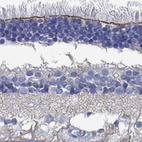

Immunohistochemical staining of human retina shows strong positivity in outer limiting membrane.